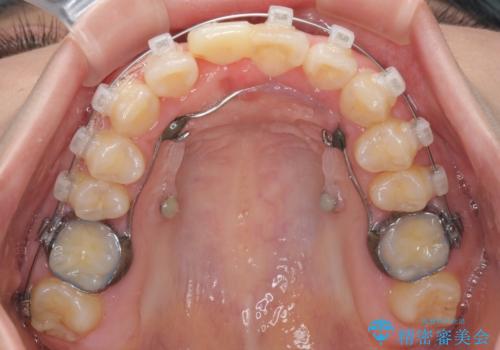

- 矯正装置

- クリアブラケット

- 中学生の頃にぶつけた前歯に不格好なクラウンが装着されており、出っ歯な印象になっていることを気にして来院された患者様です。

ぶつけてしまった歯は保存が困難な状況であったので抜歯をし、ワイヤー矯正により歯列を整えつつ前歯の突出感を解消することとしました。

矯正治療後にはインプラント補綴治療を行うこととしました。